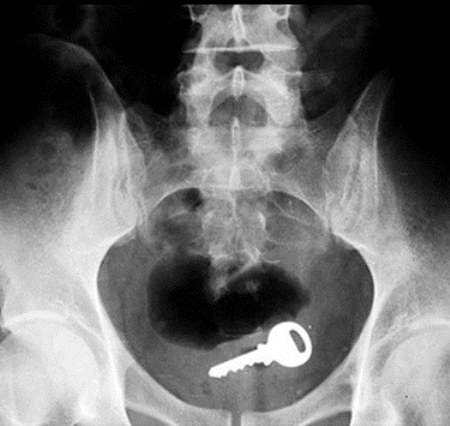

1. Uma chave